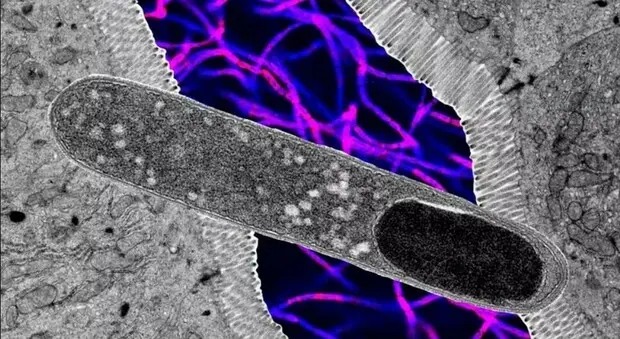

Il batterio che riduce l'aumento del peso anche in caso di diete ricche di grassi, ecco come agisce

Nella vasta comunità di batteri che popolano l'intestino umano, ne è stato individuato uno che si è dimostrato nemico dei grassi: influenza il modo con il quale sono...